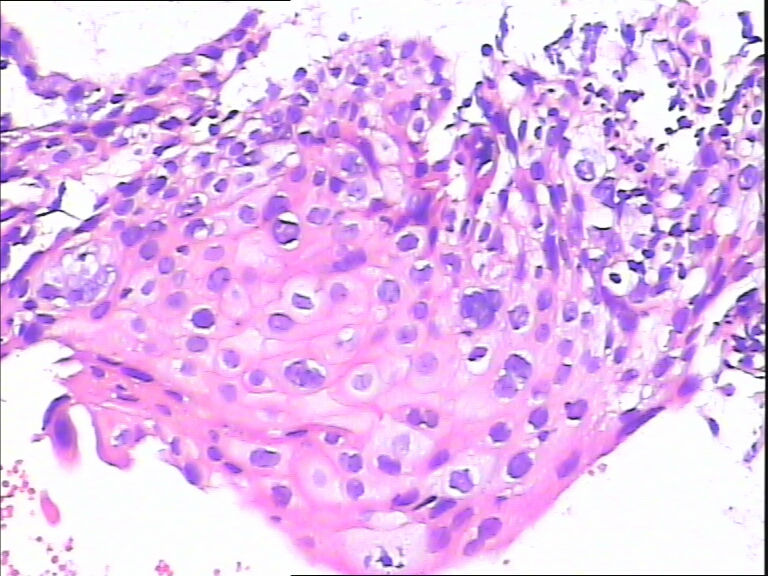

45y,触血,宫颈多点活检。

图1